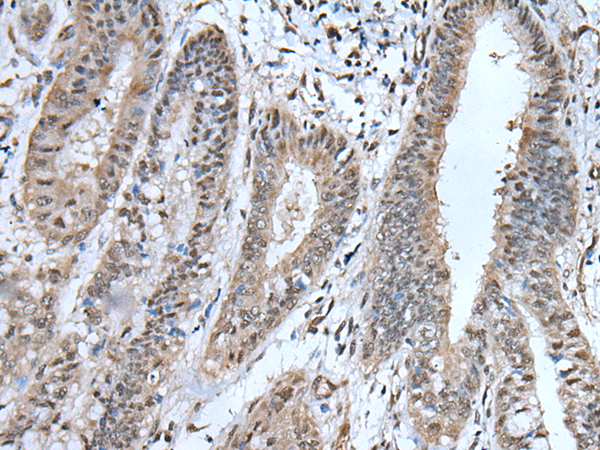

IHC positive control: |

Human liver cancer and human breast cancer |

IHC Recommend dilution: |

40-200 |